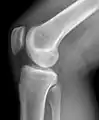

Raio-X de um joelho.